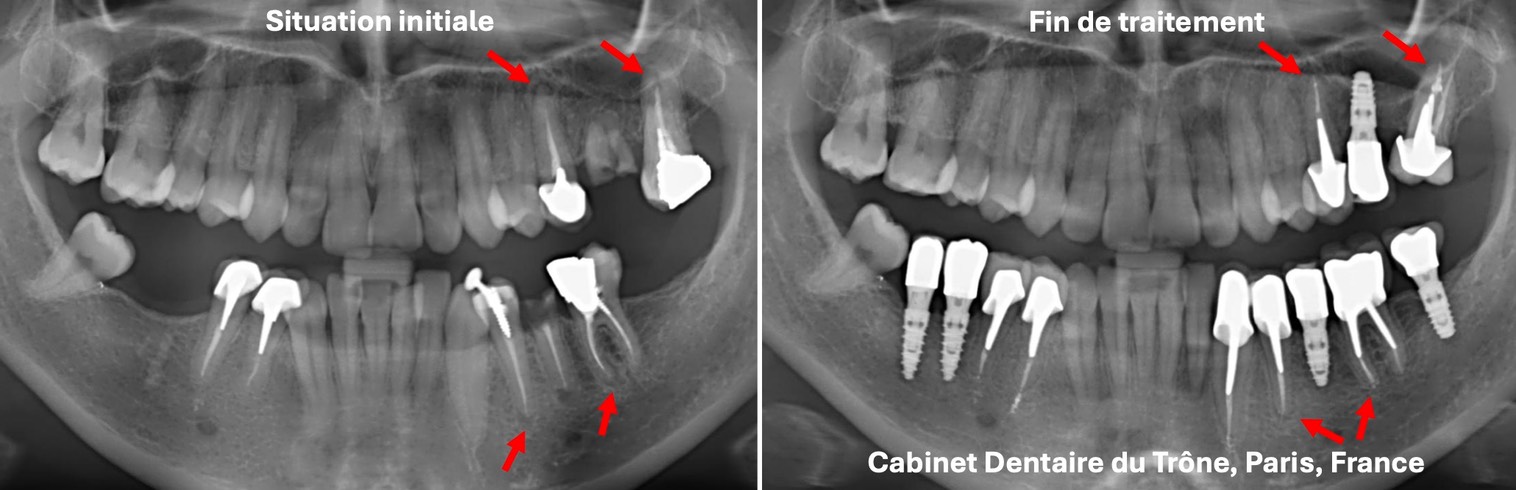

C’est la situation la plus fréquente et la plus complexe: une bouche présentant des dents absentes ou infectées à extraire, des dents cassées à sauver et de nombreux traitements anciens incomplets ou défectueux avec des kystes au bout des racines (flêches rouges ou blanches).

Le Cabinet proposera dans ces cas:

- l’élimination des dents infectées qui ne sont pas sauvables et leur remplacement par des implants (flêches blanches).

- le traitement des canaux infectés ou kystiques, puis l’assainissement des racines désinfectées et la reconstruction des dents délabrées. Au bout de quelques temps, les kystes au bout de dents vont régresser, voire disparaître (flêches rouges).